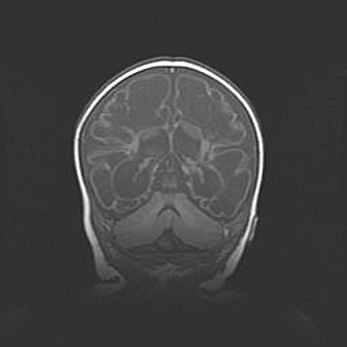

Сообщающаяся гидроцефалия. Кистозная энцефаломаляция головного мозга.

Возраст: 3 месяца 4 дня

Вес: 3100 г

Пол: женский

Окружность головы: 34 см

Срок гестации: 31 неделя

Кистозная энцефаломаляция головного мозга - одна из форм поражения головного мозга в детском возрасте. Характеризуется возникновением множественных и распространённых кист в коре, белом веществе и подкорковых образованиях головного мозга у плодов, новорождённых и детей раннего возраста. Развитие кистозной энцефаломаляции связано с внутриутробной асфиксией и гипотонией, родовой травмой, тромбозом синусов, пороками развития сосудов, инфекциями, сепсисом и другими причинами. Наиболее значимые инфекционные агенты: вирусы простого герпеса, цитомегалии, краснухи, токсоплазмы, энтеробактерии, золотистый стафилококк и другие.